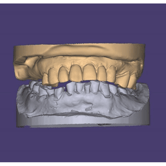

Pérdida de dimensión vertical

La pérdida de dimensión vertical ocurre cuando los dientes se desgastan o se pierden, reduciendo la altura de la mordida.

Los pacientes pueden notar una apariencia de "cara colapsada" y problemas al masticar. Esta condición puede afectar la articulación temporomandibular y la estética facial.

El tratamiento incluye restauraciones dentales para aumentar la altura de la mordida.

Inestabilidad oclusal

La inestabilidad oclusal es una mordida desequilibrada que puede causar desgaste desigual de los dientes y problemas en la articulación temporomandibular.

Los pacientes pueden notar dolor de mandíbula, dolores de cabeza y desgaste dental irregular.

El tratamiento incluye ajustes oclusales y, en algunos casos, ortodoncia o rehabilitación protésica.